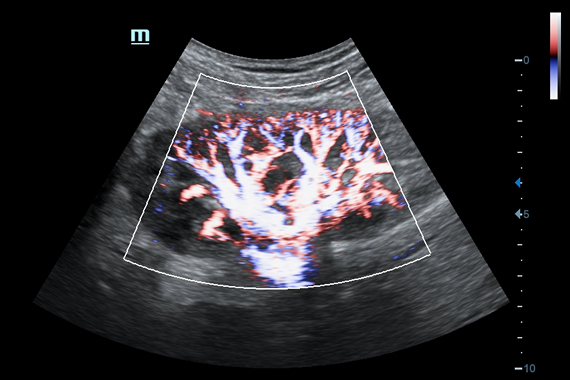

Система ультразвукового исследования Mindray DC-60 EXP X-INSIGHT является новейшей разработкой для проведения комплексных обследований на высшем уровне. Она обеспечивает решение самых сложных задач в таких областях, как кардиология, акушерство и гинекология, сосудистые заболевания, педиатрия и многие другие.

• Поддержка режимов сканирования B/M/Цветовой доплер CDI/Цветной M/Энергетический доплер PD/Направленный энергетический доплер Dir.PD.

• HR Flow - режим отображения кровотока с высоким временным и пространственным разрешением для точной и однородной визуализации сосудов, в том числе самых мелких.

Цветовой допплер:

Да